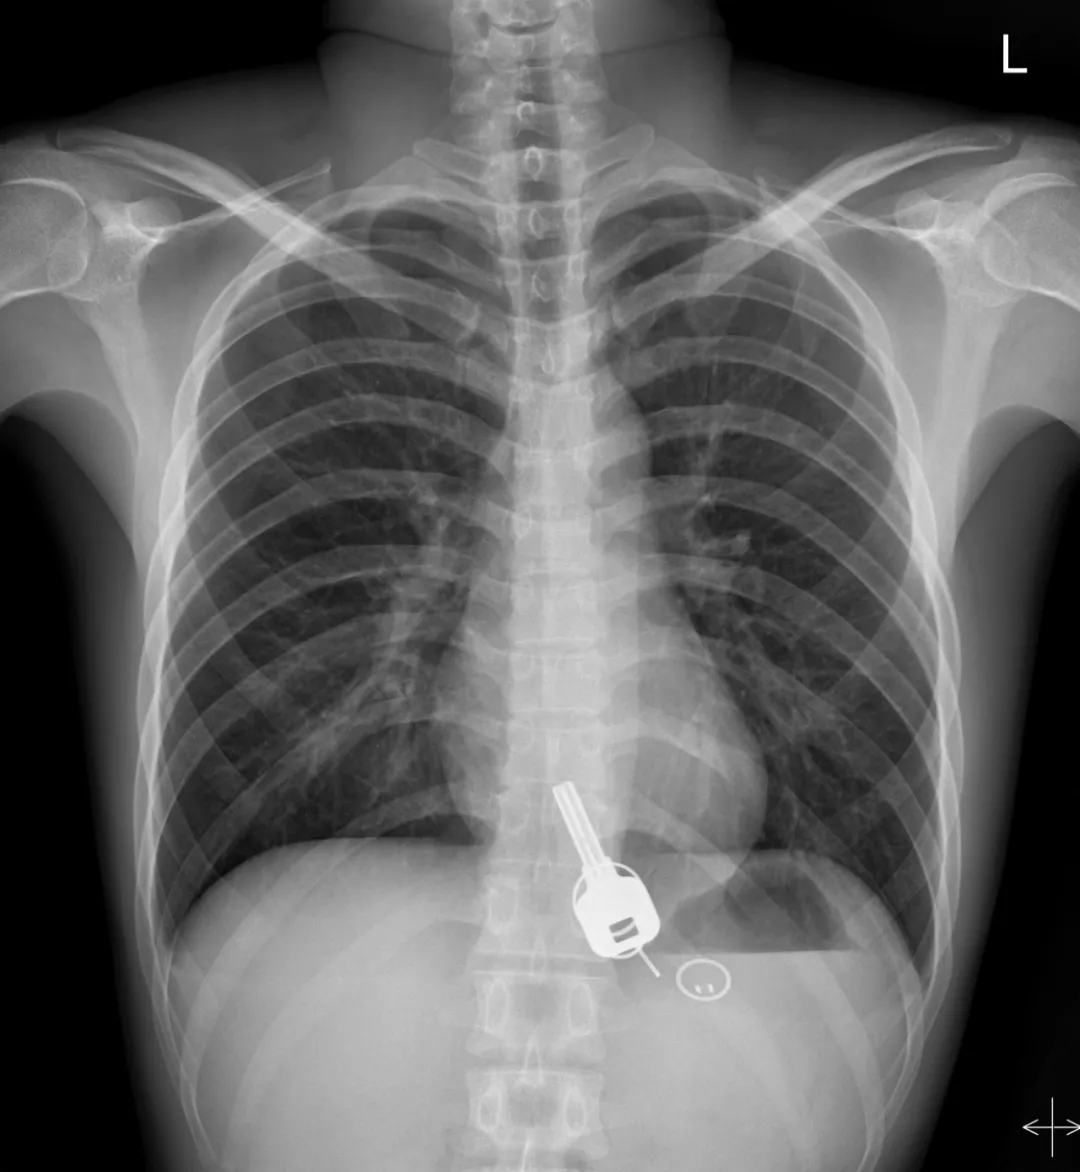

廣東東莞的常先生酒后回家找不到鑰匙,酒醒后他感到胸口疼痛,去醫(yī)院一查,發(fā)現(xiàn)一把鐵鑰匙、2個(gè)鑰匙扣、1個(gè)門禁牌清楚顯示在肚子胃區(qū)的位置上。